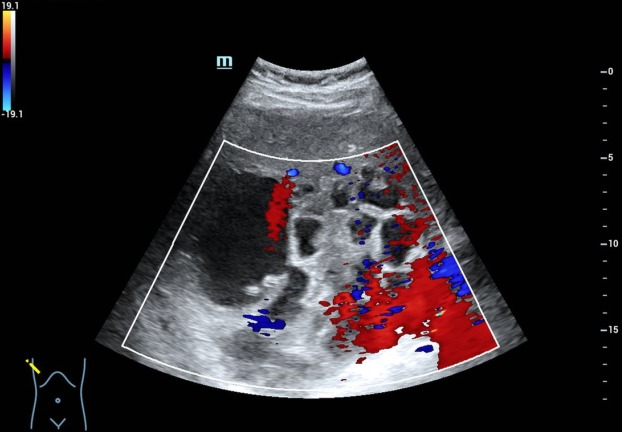

肝脏体积增大,右叶斜径约 19.0cm ,肝内可见多个厚壁无回声,大的位于肝右叶,大小约 15.5cmx13.9cm 的囊实性结节,内可见粗大分隔及壁结节,肝内胆管未见扩张。CDFI: 囊肿周边可见少许血流信号(图 1-5 )。

图 3 CDFI: 囊肿周边可见少许血流信号